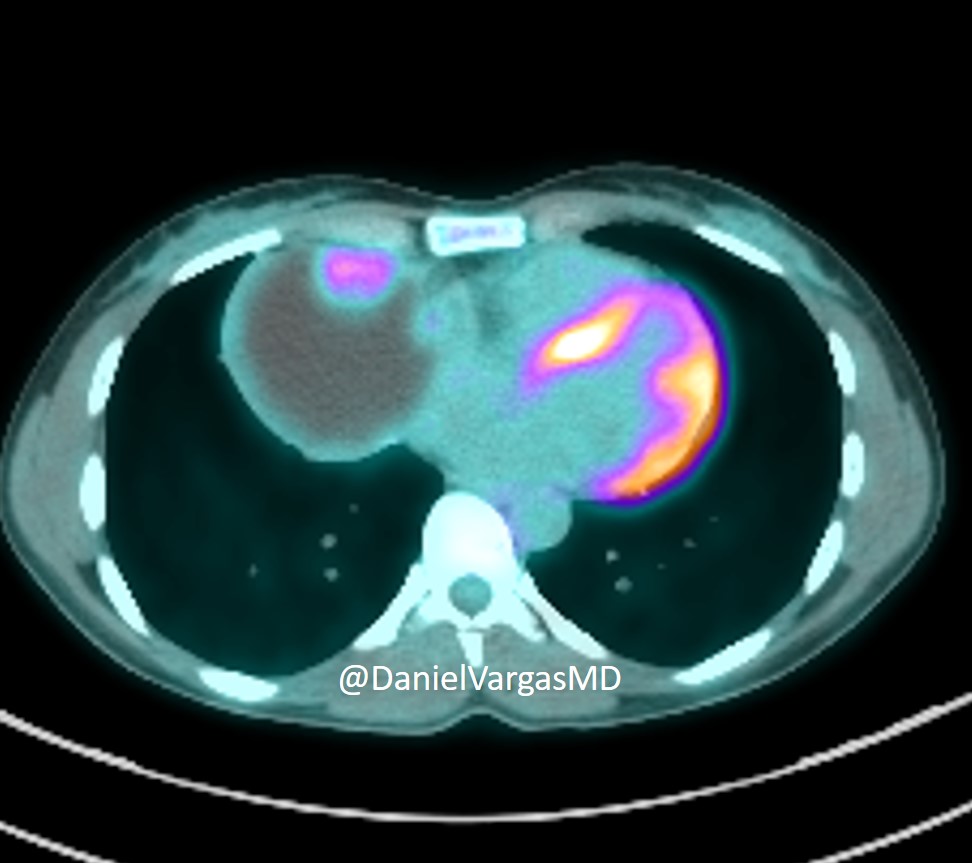

Multiple splenic hemangiomas. Most common benign neoplasm of spleen. Centripetal enhancement from periphery inward, uniform fill-in on delayed images = Similar enhancement to hepatic hemangiomas, except characteristic peripheral nodular pattern often absent. #FOAMrad #radres

Multiple splenic hemangiomas. Most common benign neoplasm of spleen. Centripetal enhancement from periphery inward, uniform fill-in on delayed images = Similar enhancement to hepatic hemangiomas, except characteristic peripheral nodular pattern often absent.

#FOAMrad #radres